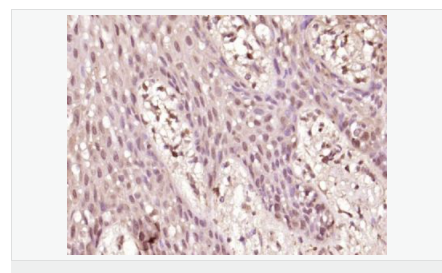

| 產(chǎn)品應(yīng)用 | WB=1:500-2000 ELISA=1:5000-10000 IHC-P=1:100-500 IHC-F=1:100-500 Flow-Cyt=1μg /test IF=1:100-500 (石蠟切片需做抗原修復(fù)) not yet tested in other applications. optimal dilutions/concentrations should be determined by the end user. |